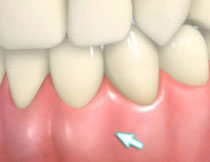

| 歯周病が進行したケースでは盲目下でポケット内の歯石を確実に除去するには限界があります。 | 局所麻酔をした後、歯茎を切開し、明視下にて歯根面の歯石や炎症組織を取り除き、歯周ポケットの除去をおこないました。 |